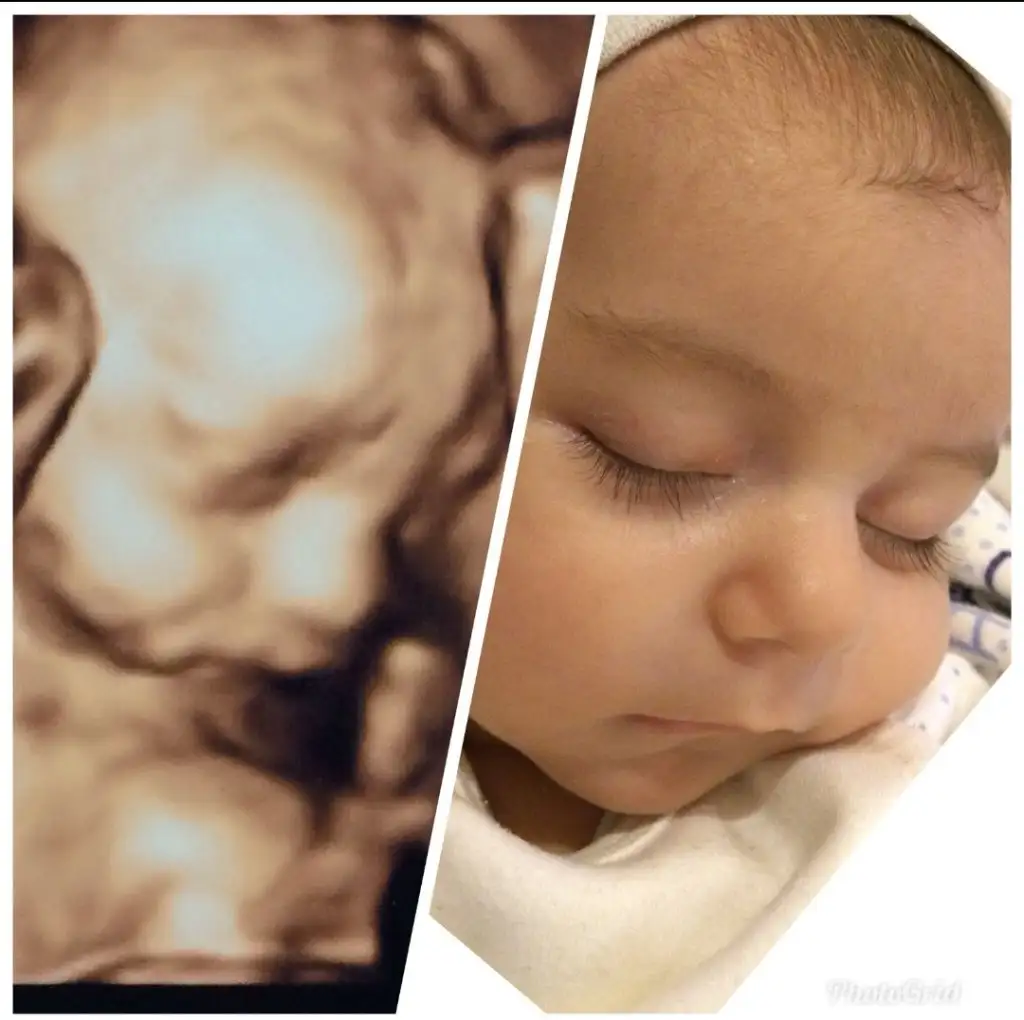

Ayyy evet o doğru bak ilk oğlumda direk aynısı çıktıAyyy bi de detaylıda gördüğün neyse çok fazla değişmiyor aynısı geliyor diyorlar

Oyy kirpiklerine maşallah onunAyyy evet o doğru bak ilk oğlumda direk aynısı çıktı